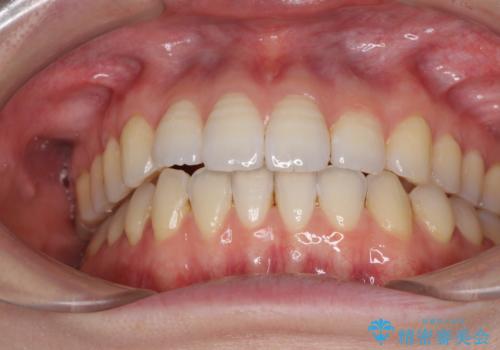

オープンバイトのインビザラインを用いた再矯正

- 矯正治療の後戻りを気にして来院された患者様です。

オープンバイト(前歯の開咬)と下顎骨の偏位による不正咬合が認められました。

骨格の偏位による不正咬合は改善しきれないことを理解いただいた上で、インビザラインにて矯正治療を行うこととしました。

オープンバイトは後戻りを起こしやすいため、極力そのリスクを軽減するため、奥歯を圧下させるように治療を進めていきました。

下顎骨の偏位が顕著であったため、上下の正中を合わせることはできませんでしたが、患者様には大変満足していただきました。